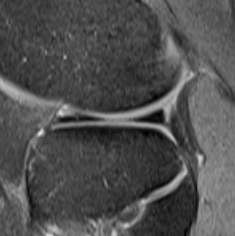

MRI

Meniscal tear + associated lateral meniscal cyst